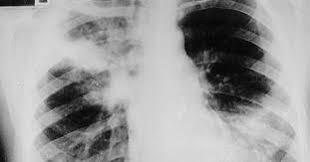

Qual a lesão clássica da TB?

Radiografia demonstrando lesão cavitária em ápice de pulmão direito.

Habitualmente representada pela TUBERCULOSE CAVITÁRIA!!

Maior pressão de oxigênio alveolar: lobo superior (lobo direito*).